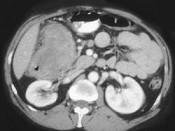

男,42岁,左下腹可触及一长条形肿块,结合图像,最可能的诊断是()A.结肠间质瘤B.结肠转移瘤C.结肠淋巴瘤D.假膜性肠炎E.结肠癌

问题 男,42岁,左下腹可触及一长条形肿块,结合图像,最可能的诊断是()

选项 A.结肠间质瘤 B.结肠转移瘤 C.结肠淋巴瘤 D.假膜性肠炎 E.结肠癌

答案 C